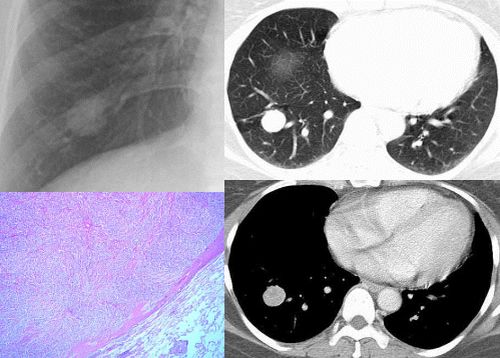

③35岁女性,因颈部包块术前检查发现右下肺圆形结节。

④男性,65岁,咳嗽、咳痰3月。

⑤男性,45岁,咳痰,痰中带血。

⑥男性,45岁。一个月前开始咳嗽。

⑦女性36y,胸痛2周住院。 手术后病理为:炎性假瘤。